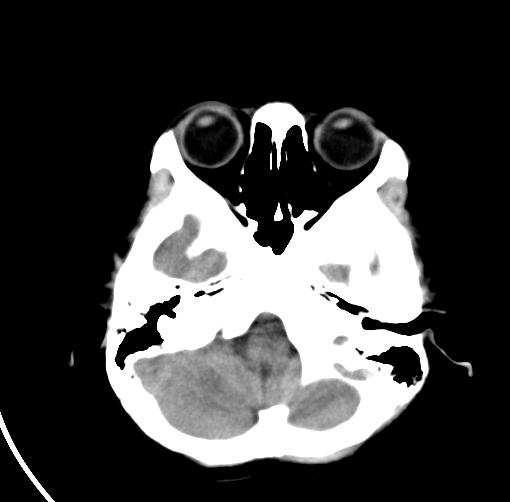

以下是引用sunjh2266在2007-7-31 23:35:00的发言:[br]脉络膜裂,是胚胎发育过程中脉络襞突入侧脑室下角构成脉络丛时形成,位于丘脑下部与海马之间,走行与海马平行。脉络裂内侧通于环池,外侧为侧脑室下角,前面是海马钩及杏仁体,后部与海马沟交通。脉络裂内有参与组成侧脑室脉络丛的脉络膜前动脉及脉络膜后外动脉及其分支走行。[br] mri轴位像,在大脑脚的前外侧多能显示脉络裂的前部,呈左右走行的含脑脊液间隙,前后内外分别与杏仁体、海马、海马钩及侧脑室下角相邻(图1);冠状位像,在扫及脑干的多个层面上,脉络裂均可被清晰显示,因而是显示脉络裂的最佳扫描方式。偏前的部分层面还可见到呈切迹状的海马沟走行于海马旁回内上方;矢状位像,海马旁回上方可见一分叉状裂隙,类似一斜卧的“入”字,接近水平走行的一撇为脉络裂,而由后上向前下走行的一捺为从扣带沟延续而来的海马沟。[br] [br]